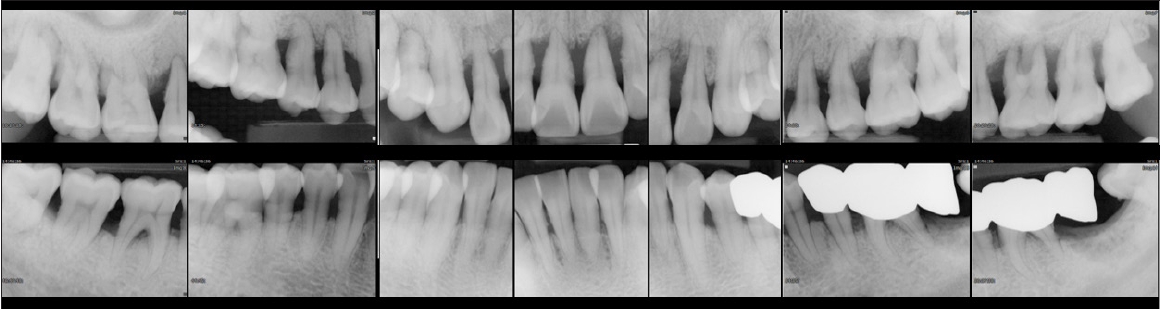

The proportion of sites with PD ≥4 mm decreased progressively over the years: 33% at baseline, 14% in 2004, 12% in 2018, and 9% in 2022 (Fig. 1). All natural teeth were preserved except for the maxillary right second molar. Serial radiographs demonstrated stable periodontal support and function throughout the 35-year follow-up period (Fig. 2).

Full-mouth distribution of probing depth (PD) at four time points: baseline in 1988, and during supportive periodontal therapy at 16 years (2004), 30 years (2018), and 34 years (2022). A progressive reduction in the proportion of sites with PD ≥4 mm was observed over the 35-year maintenance period. Representative full-mouth periapical radiographs of baseline (1988) and the most recent follow-up (2022) are also presented, demonstrating generalized alveolar bone loss at initial examination and stable periodontal support after long-term maintenance.

The 2 cases illustrate that long-term preservation of natural dentition is possible in patients with severe periodontitis when active treatment is followed by consistent and individualized supportive periodontal therapy. Both patients were maintained on a structured recall program at approximately 3 to 6 month intervals, with comprehensive periodontal evaluation, including full-mouth probing at each visit, to detect early signs of disease recurrence. This systematic approach allowed the timely detection of attachment loss and facilitated appropriate intervention.

The optimal frequency of SPT remains debated. Classic longitudinal studies suggested that intensive prophylaxis in the early healing phase, followed by 2–6-month intervals [5,10], can effectively maintain periodontal support. More recent evidence emphasizes that recall frequency should be tailored to individual risk profiles, including residual pocket depth, bleeding on probing, systemic health, and patient compliance [11,12] In these cases, recall was scheduled every 3–6 months and adjusted according to clinical stability, reflecting a pragmatic risk-based approach.

Importantly, the favorable long-term outcomes cannot be attributed to recall frequency alone. At each maintenance visit, professional care extended beyond supragingival scaling to include meticulous subgingival debridement and thorough periodontal probing. When clinical signs such as persistent pockets ≥4 mm, bleeding on probing, or radiographic bone destruction were detected, nonsurgical re-instrumentation or surgical interventions, including open-flap debridement and regenerative therapy with guided tissue regeneration, were provided [13]. Previous studies [7,14,15] have confirmed that additional SRP during maintenance can suppress disease progression, and that its effectiveness can be enhanced when combined with re-instrumentation of deep pockets or surgical access therapy. In Case 1, the timely use of open flap debridement and regenerative treatment contributed to the stabilization of periodontal support, whereas in Case 2, repeated professional tooth cleaning with ultrasonic instrumentation helped delay tooth loss for more than a decade.